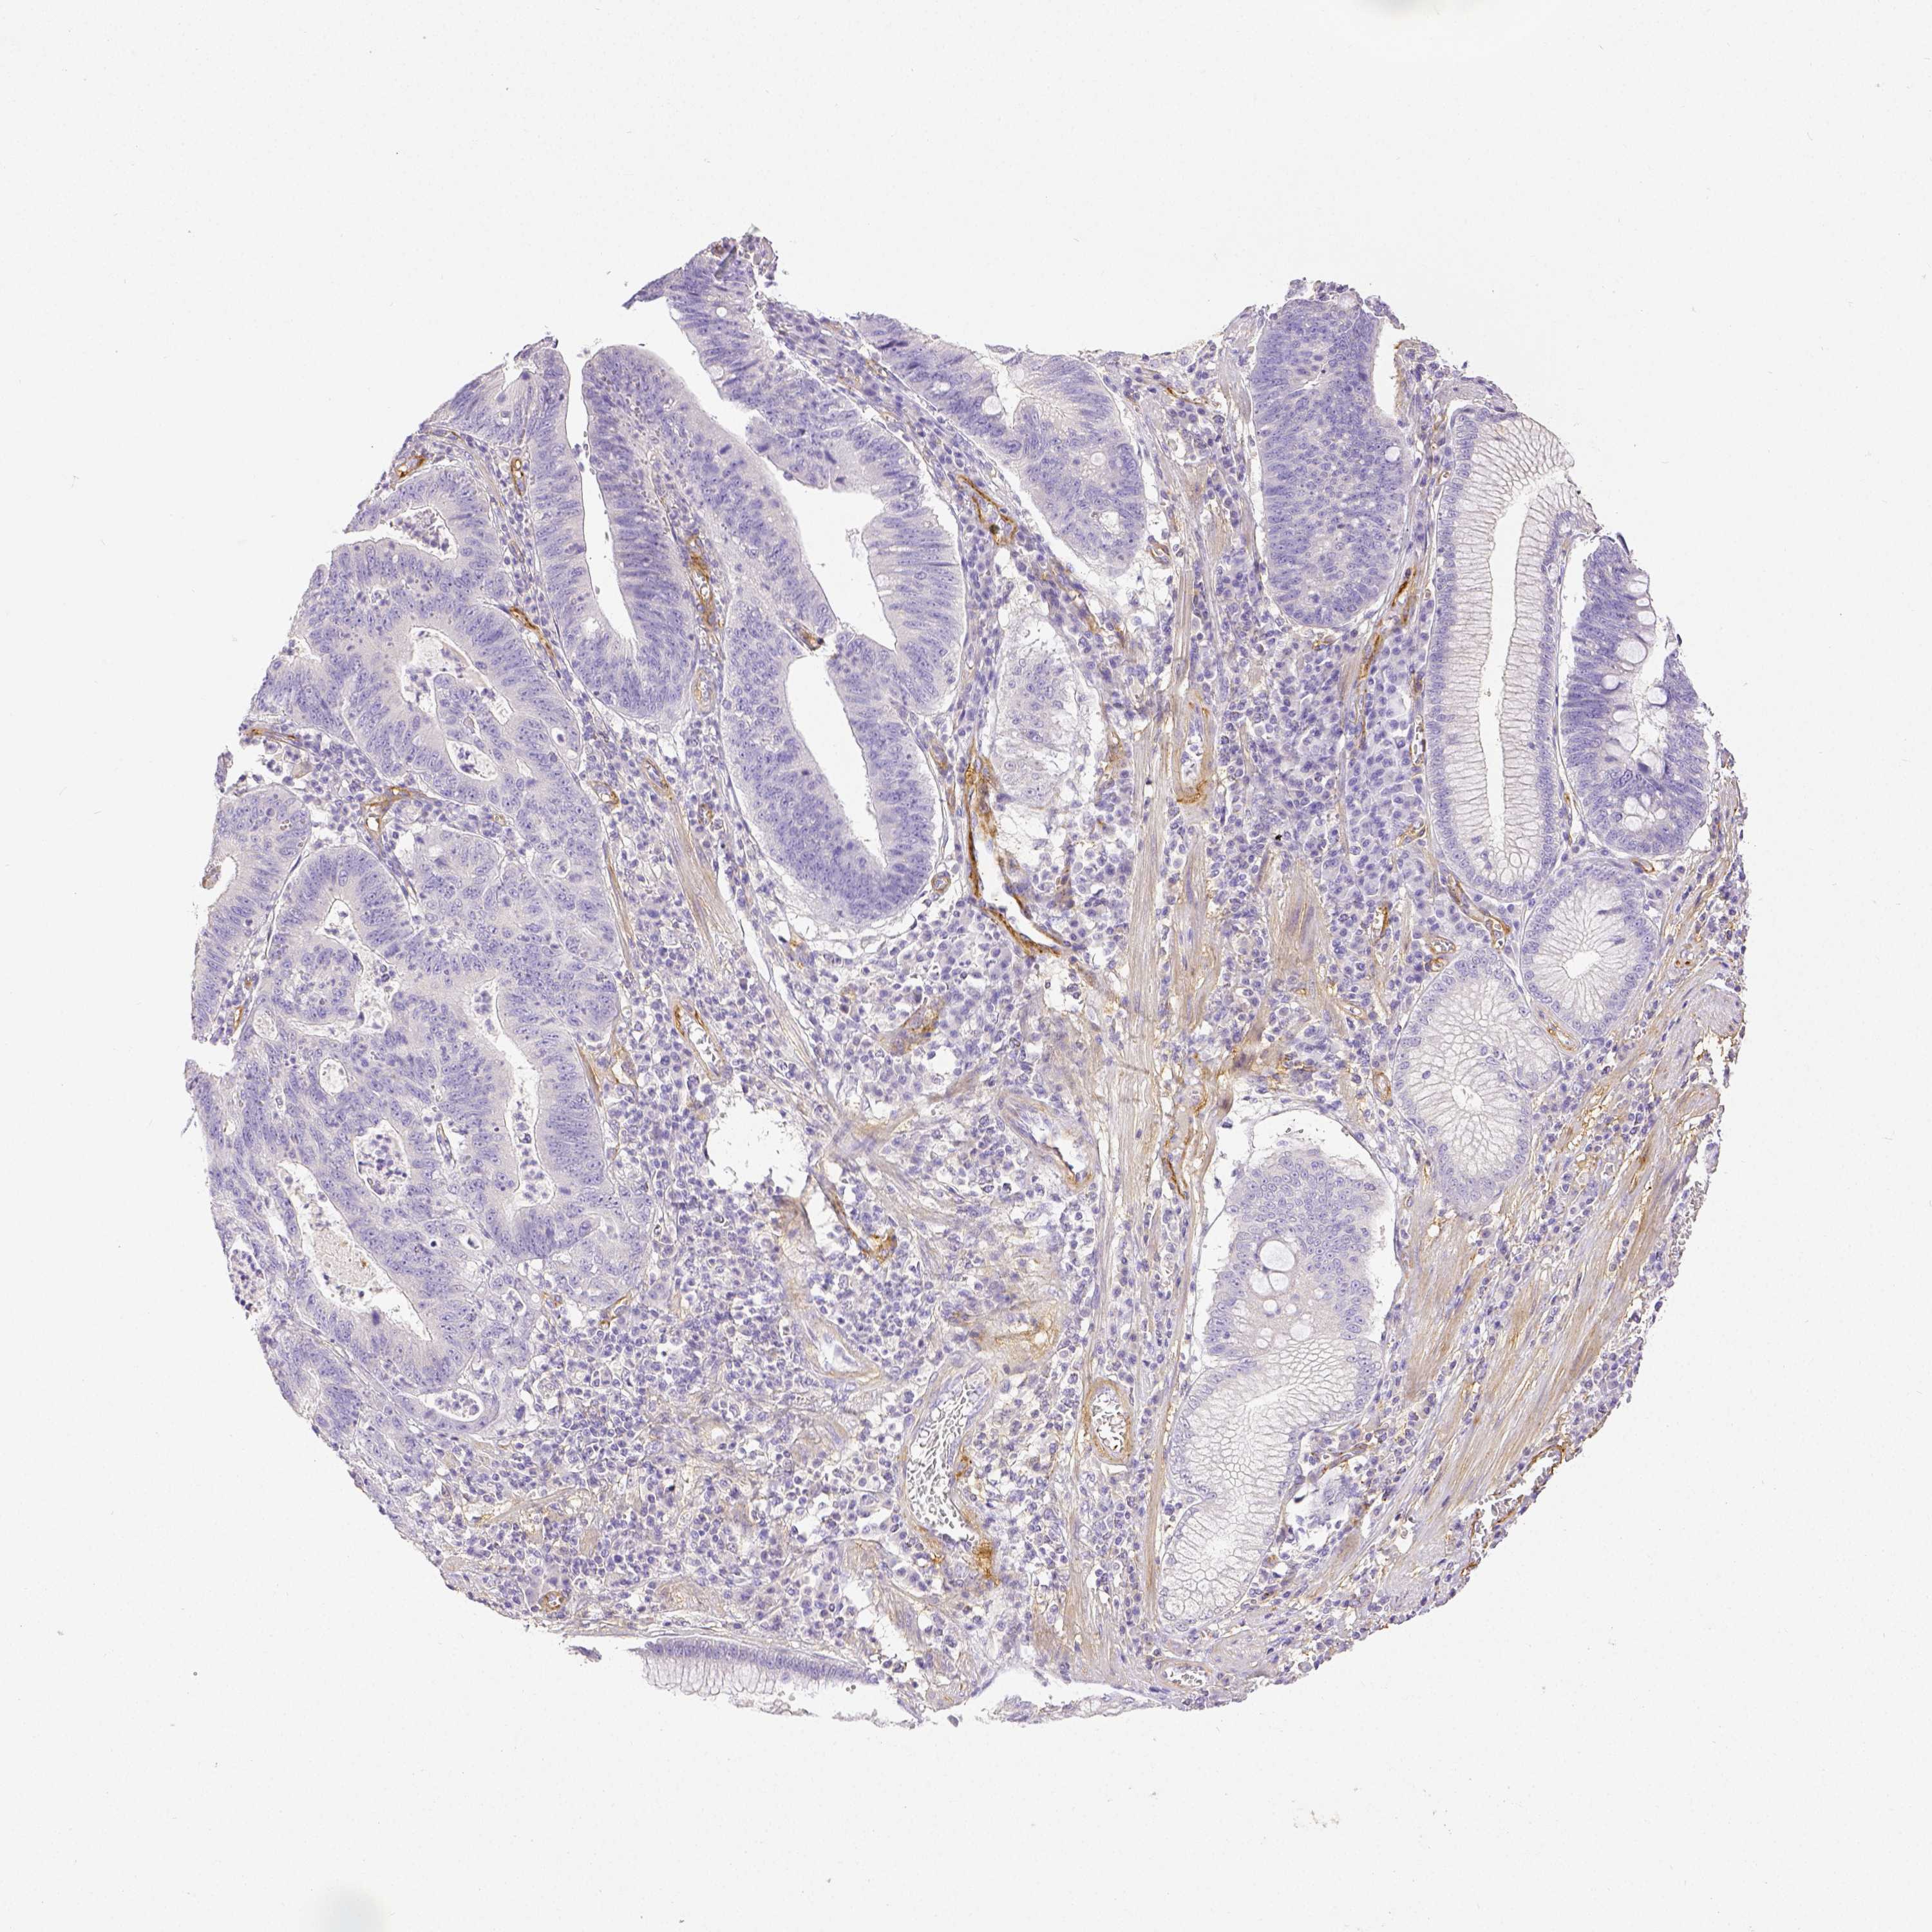

STOMACH CANCER - Protein expressioni

A mouse-over function shows sample information and annotation data. Click on an image to view it in a full screen mode. Samples can be filtered based on level of antibody staining by selecting one or several of the following categories: high, medium, low and not detected. The assay and annotation is described here.

Note that samples used for immunohistochemistry by the Human Protein Atlas do not correspond to samples in the TCGA dataset.

Antibody stainingi

Antibody staining in the annotated cell types in the current human tissue is reported as not detected, low, medium, or high, based on conventional immunohistochemistry profiling in selected tissues. This score is based on the combination of the staining intensity and fraction of stained cells.

Each image is clickable and will lead to virtual microscopy that enables deeper exploration of all samples and also displays staining intensity scores, fraction scores and subcellular localization as well as patient and tissue information for each sample.

Antibody HPA003733

Antibody CAB068243

Antibody CAB068244

Staining

High

Medium

Low

Not detected

Intensity

Strong

Moderate

Weak

Negative

Quantity

>75%

75%-25%

<25%

None

Location

Nuclear

Cytoplasmic/membranous

Cytoplasmic/membranous,nuclear

Adenocarcinoma, NOS